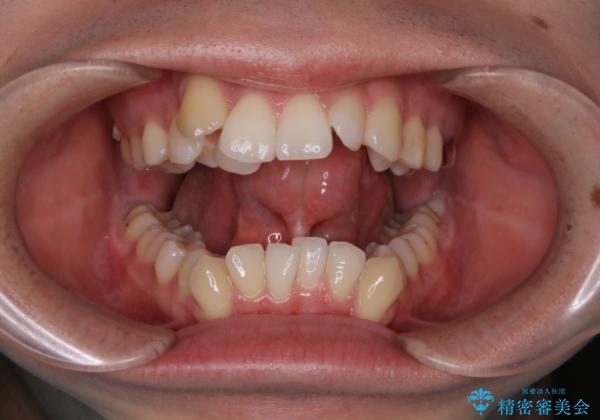

- 歯並びと滑舌が気になるとご相談にいらした方です。矯正治療に先立って、舌小帯切除を行いました。

舌小帯は、舌の下にある線維性のスジです。これが極端に短かったり、強直していると、舌の運動や発音に弊害をきたすことがあります。

切除前及び切除後には舌の機能訓練を行うことが重要です。事前に舌の訓練を行うことで切除直後のスムーズな舌運動を促し、術後にも訓練を行うことで後戻りを防止します。